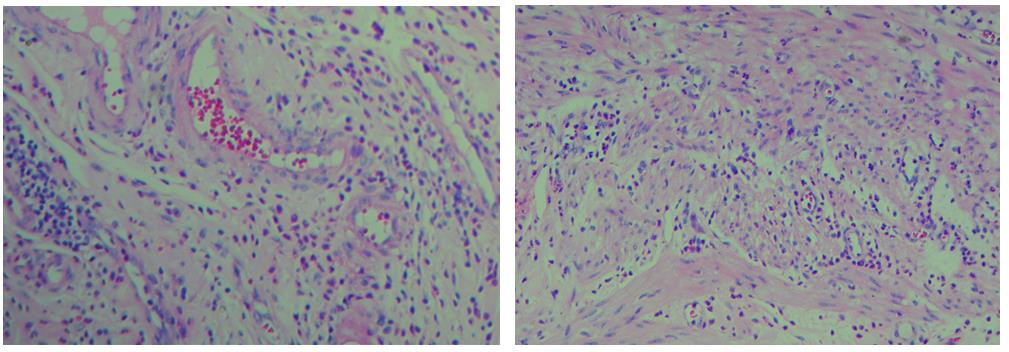

3.        色彩鮮艷,核漿紅藍對比鮮明,染色效果持久穩定,胞核結構清晰

3、色彩鮮艷,核漿紅藍對比鮮明,染色效果持久穩定,胞核結構清晰

細胞中的細胞核由帶負電荷的酸性物質組成,與帶正電荷的堿性染料蘇木素的氧化物三氧化蘇木紅有較強的親和力;而細胞漿則相反,因含有帶正電荷的堿性物質而與帶負電的酸性染料曙紅Y的親和力較強;細胞或組織切片經HE染色后,細胞核被染成藍紫色,細胞漿、紅細胞、肌纖維、膠原纖維、結締組織、嗜伊紅顆粒等被染成不同程度的紅色、粉紅色或橙紅色,與藍色的細胞核形成鮮明的對比,因此更易于觀察細胞或組織中正常成份和病變成份的一般形態結構。

【實際染色效果】